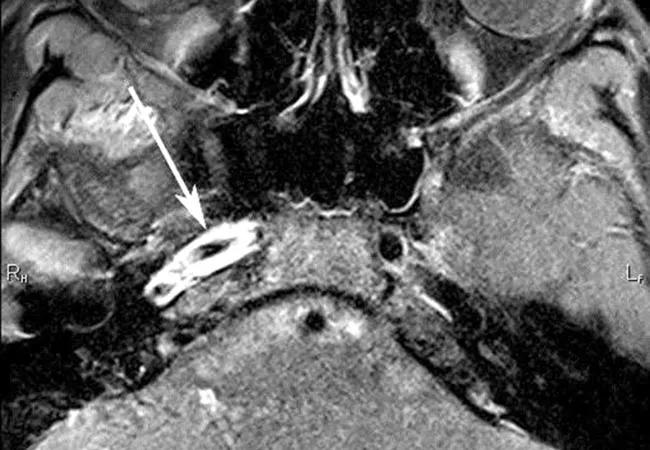

The term vasculitides describes a diverse group of diseases that result in inflammation of a blood vessel wall, which may reduce blood flow to the brain area that the blood vessel supplies. High-resolution MRI can be used to identify the most diseased segments, potentially helping target blood vessels for biopsy. The technology can also help monitor response to treatment (see Figure 2).

Figure 2. These images show resolution of contrast enhancement along the walls of the right internal carotid artery and right middle cerebral artery origin on vessel wall imaging before and after treatment of varicella zoster virus-associated vasculitis.